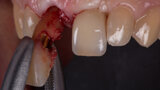

Immediate placement and restoration of a Straumann BLX implant replacing maxillary incisors